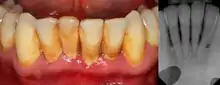

![]() | |

Gingival enlargement can be a feature in some periodontal diseases. | |